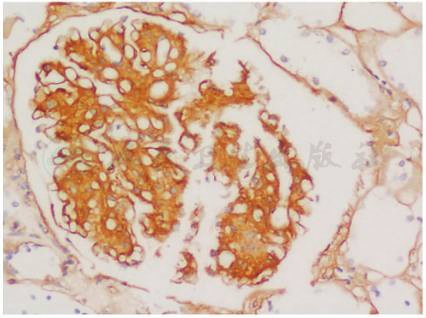

纤维连接蛋白(纤连蛋白)免疫组织化学显示肾小球系膜区和基底膜强阳性(图2)。

图2 纤连蛋白肾小球病:肾小球系膜区和毛细血管壁纤连蛋白染色阳性(免疫组化×400)

纤连蛋白肾小球病 (fibronectin glomerulopathy)是罕见的常染色体显性遗传肾小球病,也可散发。由于基因突变,导致纤连蛋白的代谢异常。常见中青年起病,临床表现不特异,主要为不同程度的蛋白尿、可有镜下血尿,血压升高,随病程进展肾功能逐渐下降,故从临床上与其他肾炎或肾病综合征不易区分,依赖超微病理诊断。光镜下肾小球系膜基质增生明显呈结节或分叶状及毛细血管壁增厚,电镜下可见大量的直径10nm左右纤维样或颗粒样物质在系膜区和内皮下沉积。但是这些亦不特异,需要与其他病理表现为结节状肾小球病的疾病鉴别,如糖尿病肾病、膜增生性肾炎、淀粉样变性、轻链沉积病及纤维样肾小球病等。确诊依靠免疫组化纤维连接蛋白阳性。

该患者为老年起病,无肾脏病家族史,临床化验未发现老年人常见的继发病因证据,然而肾活检病理发现系膜结节状硬化,电镜下看到小于10nm的纤维丝,临床除外糖尿病肾病,刚果红染色阴性除外淀粉样变性后,就应该考虑纤连蛋白肾小球病,最后免疫组化证实。